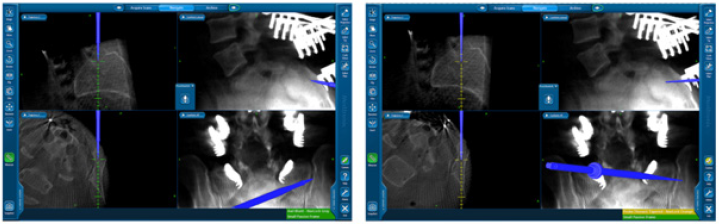

Over the last 12 years our team used image guided O-arm/ neuronavigation system for spinal fixation. 128 cases of lumbopelvic fixation were operated by myself during that time each of which had bilateral Iliac tuberosity screws insertion. Surgeries were done in prone position with patient on Jackson table, ordinary midline lumbar dissection – few cases needed extension of dissection caudad and lateral to reach the posterior superior iliac spines for the iliac tuberosity screws insertion. The navigation reference was the applied to a spinous process at the most cranial end of fixation. O-arm 3D scan was then taken, and the navigation system got registered and then screws applied starting further away from the reference to avoid offsets. In all cases we used the shortest available lateral connectors to connect the iliac tuberosity screws to the main construct together with intrarod connectors for some selected cases. Trajectory of iliac tuberosity screws is illustrated in the diagram shown in Figure 1 and Navigation snapshots shown in Figure 2.

Figure 3 shows a complex revision case of lumbosacral degenerative stenosis and scoliosis. The postoperative X-ray and CT images demonstrates the appropriate position of screws and integrity of the lumbo-pelvic fixation.